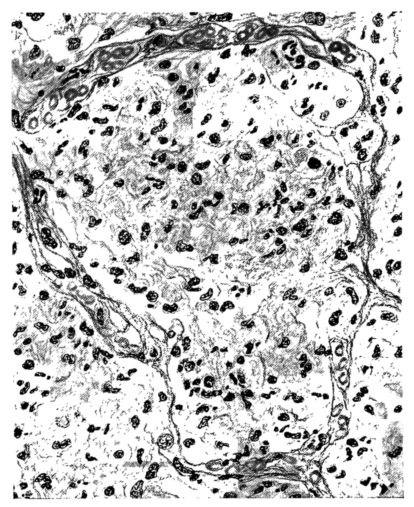

The changes are less marked, perhaps, in the trachea than in its finer ramifications. The mucosa is constantly more or less destroyed and large areas, usually focal, are entirely devoid of their epithelial covering. This is replaced by a sparse exudate, composed largely of red blood cells, mucus, a small amount of fibrin, and nuclear fragments (Fig. II). It may dip into the submucosa for a short distance, but usually these indentures are associated with the ducts of the mucous glands into which the inflammatory reaction extends. A more striking feature than the exudate, however, is the edema and the congestion of the submucosa. The loose areolar tissue of the submucosa is spread widely apart, and throughout it distended blood vessels are very conspicuous. Occasionally such a vessel is broken and actual hemorrhage appears in the submucosa. Occasionally, too, the inflammation extends down the duct to the mucous gland itself, and here, also, aplastic inflammatory reaction is evident, inasmuch as the acini now stain intensely red with the cells undifferentiated from each other and specked here and there by broken remains of the dead nuclei (Fig. III). After the disease has continued for a short period, even at the end of five or six days, some regeneration of the epithelial lining may be seen (3) (Fig. IV). But despite this, the acute picture persists, and there goes on, side by side, an attempted repair characterized by epithelial regeneration and the same evidence of acute change. Since the lesion is essentially a superficial one, scars or contractures of any extent are not encountered in the trachea, even in examples of the disease that have ended fatally only after many weeks.[4]

15There is considerable evidence to support the view that the disease spreads from bronchus to bronchus, and in keeping with this view, various stages in the inflammatory processes are more readily determined in these smaller structures than in the trachea. Furthermore, it must be emphasized that even the mildest and the most extreme of these stages are not infrequently encountered in the same lung. The earliest lesion is manifested by an increased homogeneity of the protoplasm of the epithelial lining of the bronchus. The cell protoplasm loses its normal granulation and the nucleus, somewhat darker than usual, becomes conspicuous on a red base (Fig. V). In the lumen of such a tube a serous exudate, perhaps mixed with mucus, is encountered, and there is some spreading apart of the surrounding muscular tissue with engorgement of the vessels. This picture merges gradually into one where the epithelium appears as a homogeneous, red-staining ribbon, devoid of nuclei, often exfoliated, in part at least, from the underlying submucosa (92). The change is traceable through the larger bronchi, even to the ducti alveolares, and not infrequently, bacteria, either as a diffuse, minute dotting or in the form of circumscribed, colony-like formations, are spread through the red, ribbon-like strand (Fig. XVI). With the exfoliation of the epithelial lining, the submucous vessels become more and more conspicuous and may bulge into the lumen of the tube (Fig. VI). That they actually weep into the lumen is proved by the presence of red blood cells in the exudate, now rich in mucus, broken-down nuclei, and desquamated cells. The necrotizing process may not extend deeper than the epithelial lining as is the status described above (140, 162), but it also frequently involves the underlying submucous and muscular layers, so that these lose their identity and stand out as homogeneous masses, in which fragmented nuclei and bacterial accumulations are prominent. Such deeper necrotizing areas may be focal (Fig. VII), or may involve the entire circumference of the tube (Fig. VIII). Occasionally, the epithelium, now dead and staining homogeneously, is lifted from the underlying submucosa in the form of a blister (66), and has very much the same appearance as the well known, early reaction which follows the application of croton oil to the rabbit’s ear. Where this occurs, the submucosa is less involved, as though the necrotizing agent had not penetrated to the same depth and the serous reaction beneath were actually a beneficent exudate. These blisters are in contrast with the deeper areas where the fibrinous mass, mixed with the dead tissue, forms an intensely staining ring or band, which extends through the bronchiolar wall even to the surrounding alveoli.

In the early stage of this process one of the most outstanding features is the absence of polynuclear leucocytes in the reactionary process, but gradually as the dead tissue sloughs away, these cells wander into the exudate and form a purulent ring, more intense in the lumen, but extending for a variable distance through the still viable wall of the structure (47) (Fig. IX). Later mononuclear cells accumulate in this wall and occur either as a diffuse mottling or as circumscribed foci in the muscle and submucous layer of the bronchiole, just as they do in the trachea. Occasionally, a striking change is found in a small bronchiole within a portion of the lung which is otherwise uninvolved by an inflammatory process. Perhaps the alveoli were the seat of a change which has subsided, but, whatever the history, the purulent mass in the bronchiole and involving its wall, stands out effectively (Fig. X).